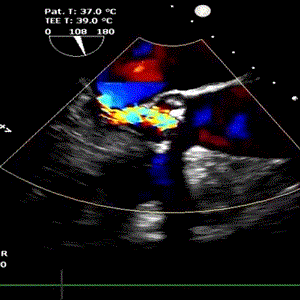

患者女性,75岁,因“反复胸闷、胸痛1年余”入院。超声心动图示主动脉瓣重度狭窄钙化,伴中重度关闭不全。CT显示主动脉瓣为Type 1型二叶瓣,且无冠瓣与左右冠瓣融合嵴形成“T型”钙化结构,属TAVI挑战病例。瓣环平均直径22.5mm,瓣环面积402.0mm²。左冠脉开口高度11.8mm,右冠脉开口高度11.0mm。术前TEE示峰值流速4.9m/s,平均跨瓣压差54mmHg,有强烈手术指征。

9月27日上午10时,直播开始,魏来教授团队耗时约1小时,经右侧股动脉植入23# Renatus介入主动脉瓣。瓣膜植入位置理想,功能表现出色,造影及经食道超声观察显示瓣膜无中央性返流,轻微瓣周漏,无冠脉血流受阻,无传导阻滞,主动脉瓣峰值流速降至2.0m/s,平均跨瓣压差降至7mm/Hg。手术取得圆满成功。

术前心脏彩超                               术后心脏彩超

术后经食道超声